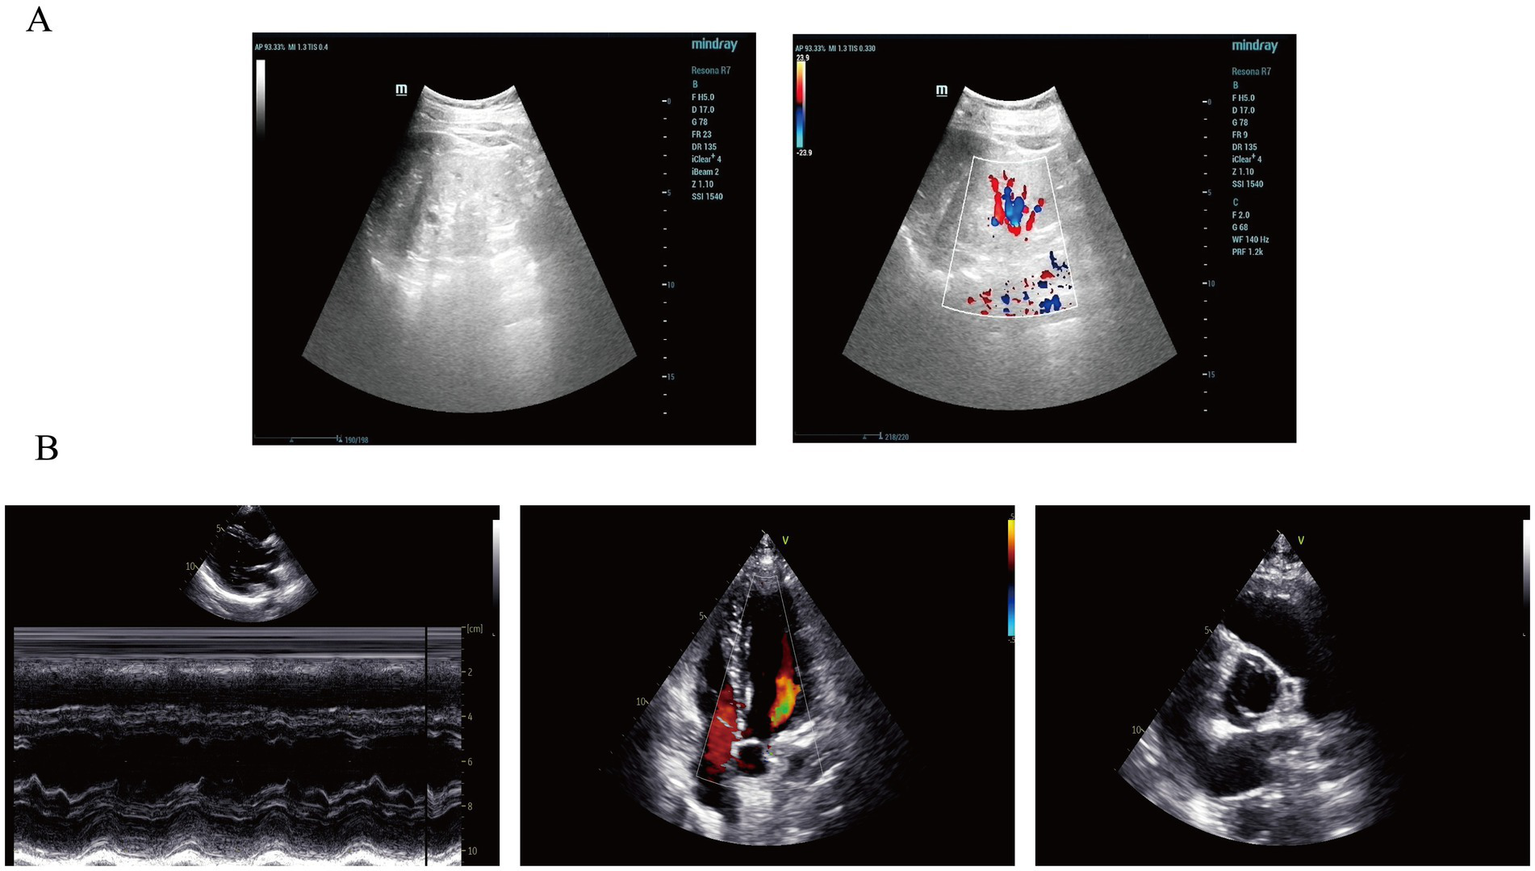

A 21-year-old male presented with proteinuria that first manifested 6 years ago without an identifiable cause. At that time, no further medical assessment or treatment was pursued. Four years ago, an evaluation of renal function at an external hospital revealed an elevated serum creatinine level of 170.00 μmol/L. Subsequent follow-up indicated a gradual increase in serum creatinine levels. He intermittently took Haikun Shenxi Capsules (two capsules, three times daily), a traditional Chinese medicine preparation primarily composed of fucoidan sulfate polysaccharide, which is clinically utilized for the treatment of chronic renal failure. Its reported therapeutic effects include improvement of renal blood flow, attenuation of glomerulosclerosis, promotion of renal function recovery, scavenging of reactive oxygen species, and inhibition of lipid peroxidation (14). Four months prior to admission, the patient’s serum creatinine level rose to 421.54 μmol/L, and his hemoglobin level was recorded at 113.00 g/L. Roxadustat was subsequently introduced to address renal anemia. Two weeks before admission, the patient experienced bone pain accompanied by pruritus. Laboratory tests revealed a parathyroid hormone (PTH) level of 627.50 pg./mL, urea 25.75 mmol/L, creatinine 598.51 μmol/L, and estimated glomerular filtration rate (eGFRcr) of 11.06 mL/min/1.73 m2. Serum inorganic phosphorus was 1.55 mmol/L. He was treated with sevelamer and calcitriol, which led to partial relief of pruritus and bone pain. However, renal function deteriorated significantly. Ten days prior to the latest evaluation, serum urea increased to 31.30 mmol/L and creatinine to 946.77 μmol/L, with an eGFRcr of 6.38 mL/min/1.73 m2. Urinalysis revealed “++” proteinuria, with a 24-h urine protein excretion of 1220.67 mg/24 h. PTH level was 253.10 pg./mL (Figure 1). B-mode ultrasonography of the urinary system revealed multiple anechoic lesions in the bilateral renal cortices, consistent with bilateral renal cysts (Figure 2A). The patient had a history of hypertension lasting over 4 years, with maximum readings of 140–150/100–90 mmHg. Initially, blood pressure was managed with valsartan capsules; however, due to suboptimal control, the treatment was switched to benidipine, resulting in improved blood pressure stability. Additionally, the patient had a previous diagnosis of hypothyroidism and was regularly taking levothyroxine at a dosage of half to three-quarters of a tablet daily. Transthoracic color Doppler echocardiography (CDE) revealed a bicuspid aortic valve (type I, R/L), characterized by the fusion of the right and left coronary cusps arranged in a left–right orientation, with a commissural angle of approximately 160°. A fused ridge was noted between the fused leaflets, which opened well but exhibited a visible raphé (Figure 2B). Chest and upper abdominal CT scans no significant abnormalities. During the evaluation, the patient exhibited mildly delayed cognitive development compared to peers. However, no overt dysmorphic features or neurological signs were observed.

Figure 2

Imaging findings of the patient in this case report. (A) Renal ultrasonography revealed multiple anechoic lesions in the renal cortex. In the right kidney, the largest cyst was located at the lower pole, measuring 0.8 × 0.5 cm, with well-defined margins and good internal echogenicity. In the left kidney, multiple cortical cysts were observed, with the largest measuring 1.0 × 0.8 cm in the mid-region, showing clear margins and good posterior acoustic enhancement. These findings are consistent with bilateral renal cysts. (B) Color Doppler echocardiography (CDE) demonstrated normal sizes of all cardiac chambers, with no thickening of the interventricular septum or left ventricular wall, and preserved wall motion. The aortic valve showed fusion of the left and right coronary cusps, arranged in a right–left orientation with a commissural angle of approximately 160°. A fusion ridge was visible between the fused cusps, with good valve opening and a commissural slit, indicating a congenital bicuspid aortic valve (right–left, Type I). The morphology and structure of the remaining valves appeared normal.